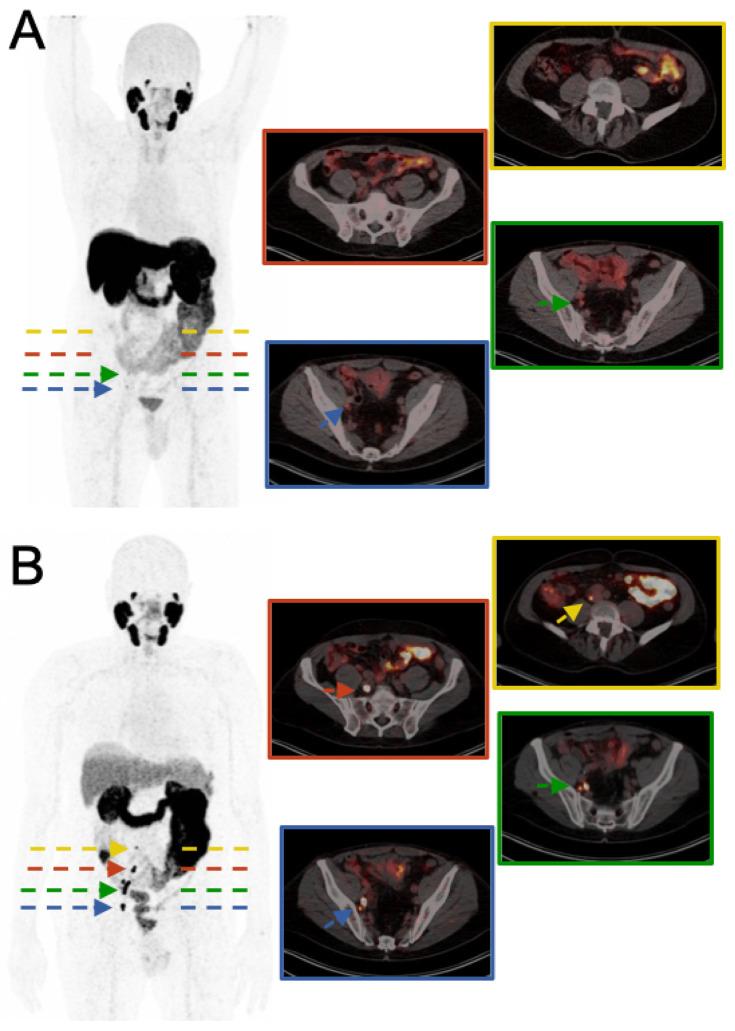

We report a case of a 79-year-old male patient with a history of radical prostatectomy for prostate cancer. The patient presented with biochemical reoccurrence; however, previous conventional PSMA PET/CT using [F]PSMA-1007 showed two indetermined findings with low uptake in the right iliac lymph nodes. Further MRI evaluation provided no additional information. A recently introduced PSMA tracer, [Zr]Zr-PSMA-617 (half-life: 3.3 days), was administered in an attempt to confirm the diagnosis and aid in potential radiation planning. [Zr]Zr-PSMA-617 PET/CT clearly revealed the previously indetermined right iliac lymph nodes as definitely metastatic and also identified additional lymph node metastases that were undetected in prior scans. This case highlights the potential superior sensitivity of [Zr]Zr-PSMA-617 PET/CT in detecting recurrent disease, especially in unclear settings of [F]PSMA-1007 PET/CT and demonstrates its potential for guiding targeted radiation therapy with curative intent.

我们报告一例79岁男性患者,有前列腺癌根治术病史。该患者出现生化复发;然而,之前使用[F]PSMA - 1007进行的传统PSMA PET/CT显示右侧髂淋巴结有两个摄取低的不确定结果。进一步的MRI评估未提供更多信息。为了确诊并辅助潜在的放射治疗计划,使用了一种最近引入的PSMA示踪剂[Zr]Zr - PSMA - 617(半衰期:3.3天)。[Zr]Zr - PSMA - 617 PET/CT清楚地显示之前不确定的右侧髂淋巴结确实已转移,还发现了之前扫描未检测到的其他淋巴结转移灶。该病例突出了[Zr]Zr - PSMA - 617 PET/CT在检测复发性疾病方面潜在的更高敏感性,尤其是在[F]PSMA - 1007 PET/CT结果不明确的情况下,并证明了其在指导有治愈意图的靶向放射治疗方面的潜力。